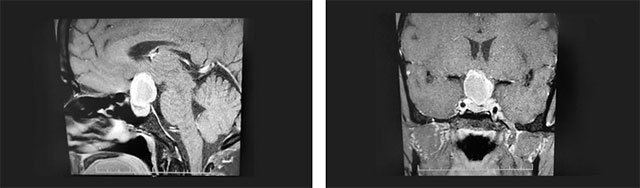

头颅鞍区MRI平扫+增强显示:鞍区见团块状异常信号影,大小约2.6*2.1*2.5cm。瘤灶向上突入鞍上池、第三脑室受压,鞍隔受压下塌,垂体上缘受压变扁。鞍底骨质略下陷,视交叉上抬、分界不清。

▲ 术前影像:垂体大腺瘤,向鞍上生长